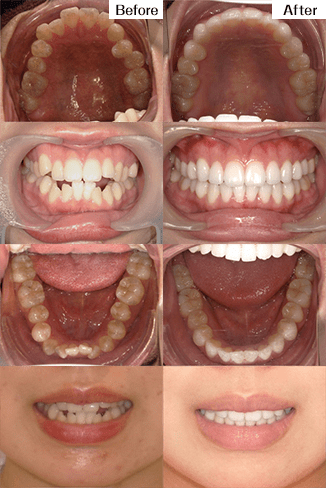

(インビザライン)治療の説明 主訴:叢生 年齢 32歳 抜歯箇所 なし 治療期間 1年1ヶ月 通院回数 10回 ![]()

治療費用 767,800円 治療の内容・詳細 初回と追加アライナーで主訴の叢生を改善、最終左上2番の挺出と嚙み合わせの調整を行い治療を終了いたしました。 治療の副作用(リスク) 保定装置をしっかり装着していないと、後戻りする可能性があります。咬合痛、歯根吸収、歯根露出を生じる可能性があります。